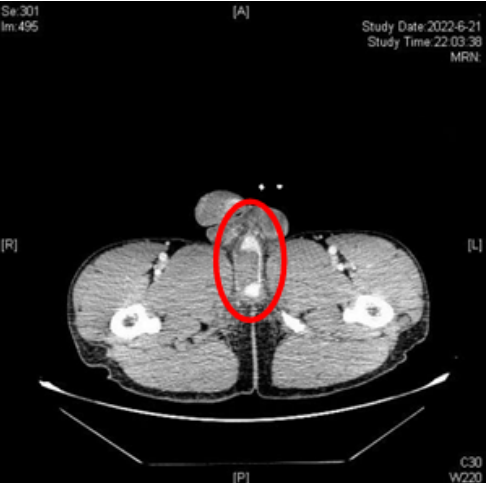

,急诊CT发现刘强阴茎海绵体撕裂、尿道海绵体断裂、会阴软组织挫伤、血肿、左侧第11-12肋骨骨折,泌尿外科会诊后随即行急诊手术,将断裂尿道进行修补。

CT示患者阴茎海绵体部分撕裂,尿道海绵体断裂、造影剂外漏,海绵体周围软组织挫伤